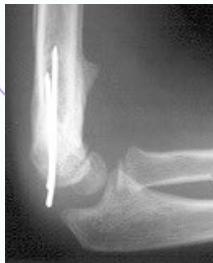

Case Example: 6-year-old girl, fell from swing

3 months follow-up